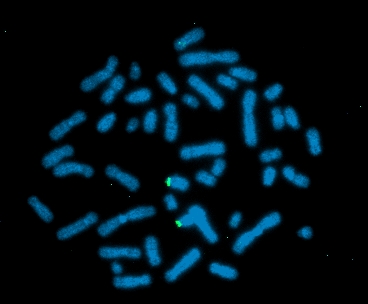

FISH FITC detects DXZ1, DAPI counterstain |